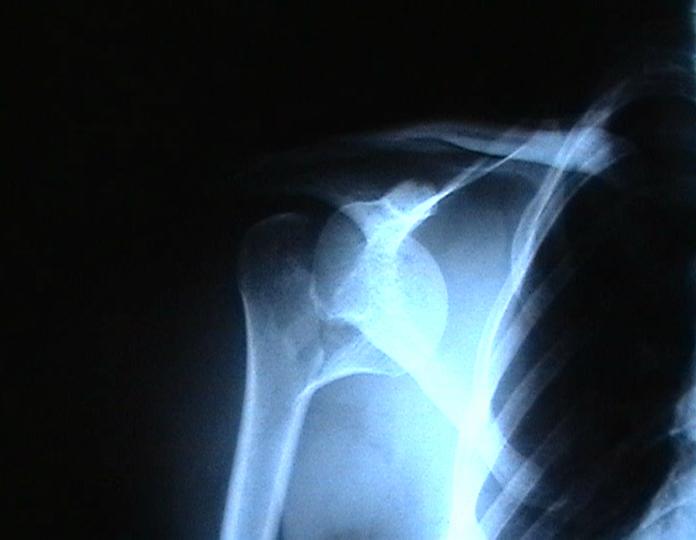

Мужчина 25 лет 16 августа 2002 г. в автоаварии получил перелом шейки плеча (снимок 1); 5 сентября в городской больнице выполнен остеосинтез пластинкой (снимок 2).К настоящему времени попал к нам на разработку ввиду выраженной контрактуры плечевого сустава. В течение последнего месяца беспокоят умеренные боли в области плечевого сустава, усиливающиеся при разработке, еще и торчит край пластинки. Нынешняя рентгенологическаякартина на снимках 3 и 4. Головка плеча уменьшается, сращение сомнительное.Кроме удаления пластинки, что еще на сегодня целесообразно сделать?Заранее спасибо.

Согласен с вашим мнением -асептический некроз головки плеча. Есть ли у вас надежды на реваскуляризацию головки ? Если надеетесь, то имеет смысл продолжать физио, если нет, то следует думать опротезировании.

I think the AVN is at least stage 3 with deformity of the head. I would advise a removal of implant and a cementless humeral head replacement. Or if you have the experience and the implant, as well as adequate bone stock, maybe a resurfacing prosthesis like the Copeland shoulder. I am not sure if you can do it one or two stages. You can perhaps do it in one stage if there is no sign of infection and if the patient condition allows it. You should not worry too much about age since this is a non